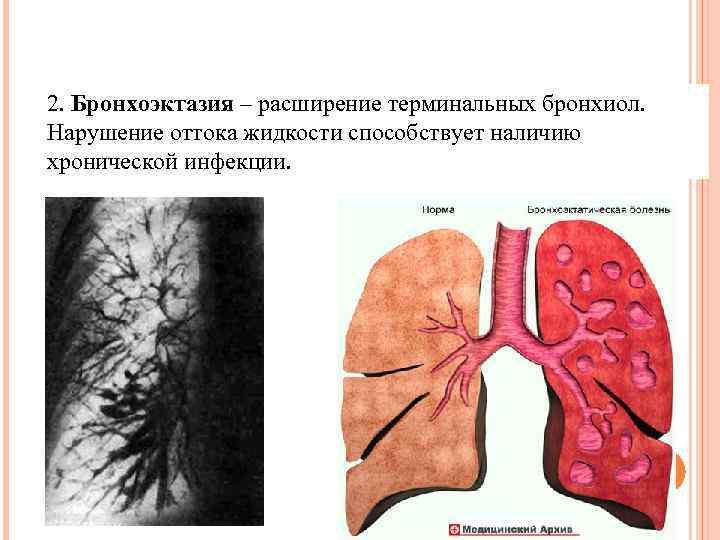

2. Бронхоэктазия – расширение терминальных бронхиол. Нарушение оттока жидкости способствует наличию хронической инфекции.

2. Бронхоэктазия – расширение терминальных бронхиол. Нарушение оттока жидкости способствует наличию хронической инфекции.